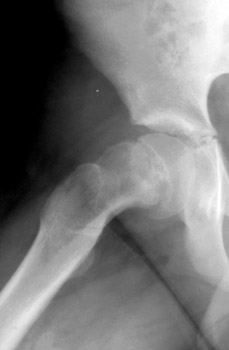

Skeletal Trauma > Pelvis & Hips > Slipped Femoral Epiphysis

Slipped Femoral Epiphysis